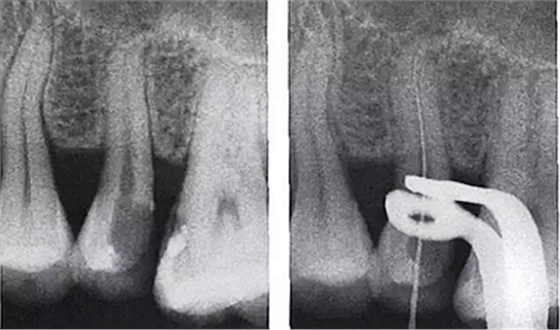

5.用X線片輔助確認(rèn)